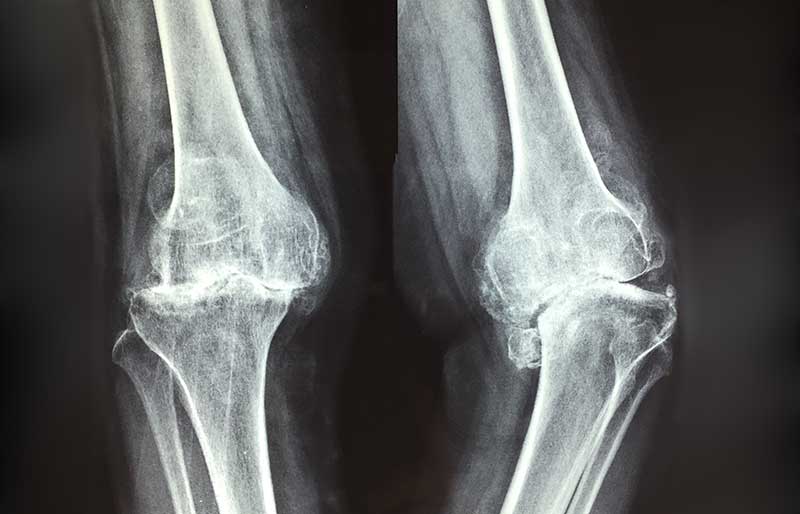

Kerusakan dan penipisan tulang rawan memicu terjadinya proses peradangan sendi (melalui terbentuknya beberapa zat kimia tertentu di dalam sendi), sehingga sendi terasa nyeri dan kadang-kadang membengkak. Jika penipisan semakin berat sehingga tulang rawan hilang sama sekali, maka ujung tulang pembentuk sendi saling bergesekan secara langsung sehingga menimbulkan rasa nyeri yang berat dan gangguan mekanis berupa bunyi “krek-krek” dan sendi menjadi kaku.

Pada stadium awal, keluhan penderita osteoartritis berupa nyeri dan kaku sendi setelah lama tidak bergerak; sebagai contoh, lutut terasa sakit dan kaku saat bangun tidur, saat berdiri dari posisi duduk atau saat turun dari mobil, atau saat berjongkok. Lutut juga terasa sakit jika digunakan naik atau turun tangga. Pada stadium yang lebih berat, lutut terasa sakit saat dipakai berjalan, terutama jika berjalan jauh. Sering terdengar bunyi “krek- krek” saat sendi digerakkan.